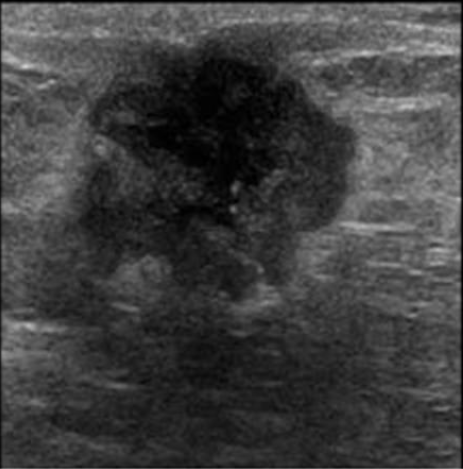

Q

Sugestivo de… ?

A

Maligno